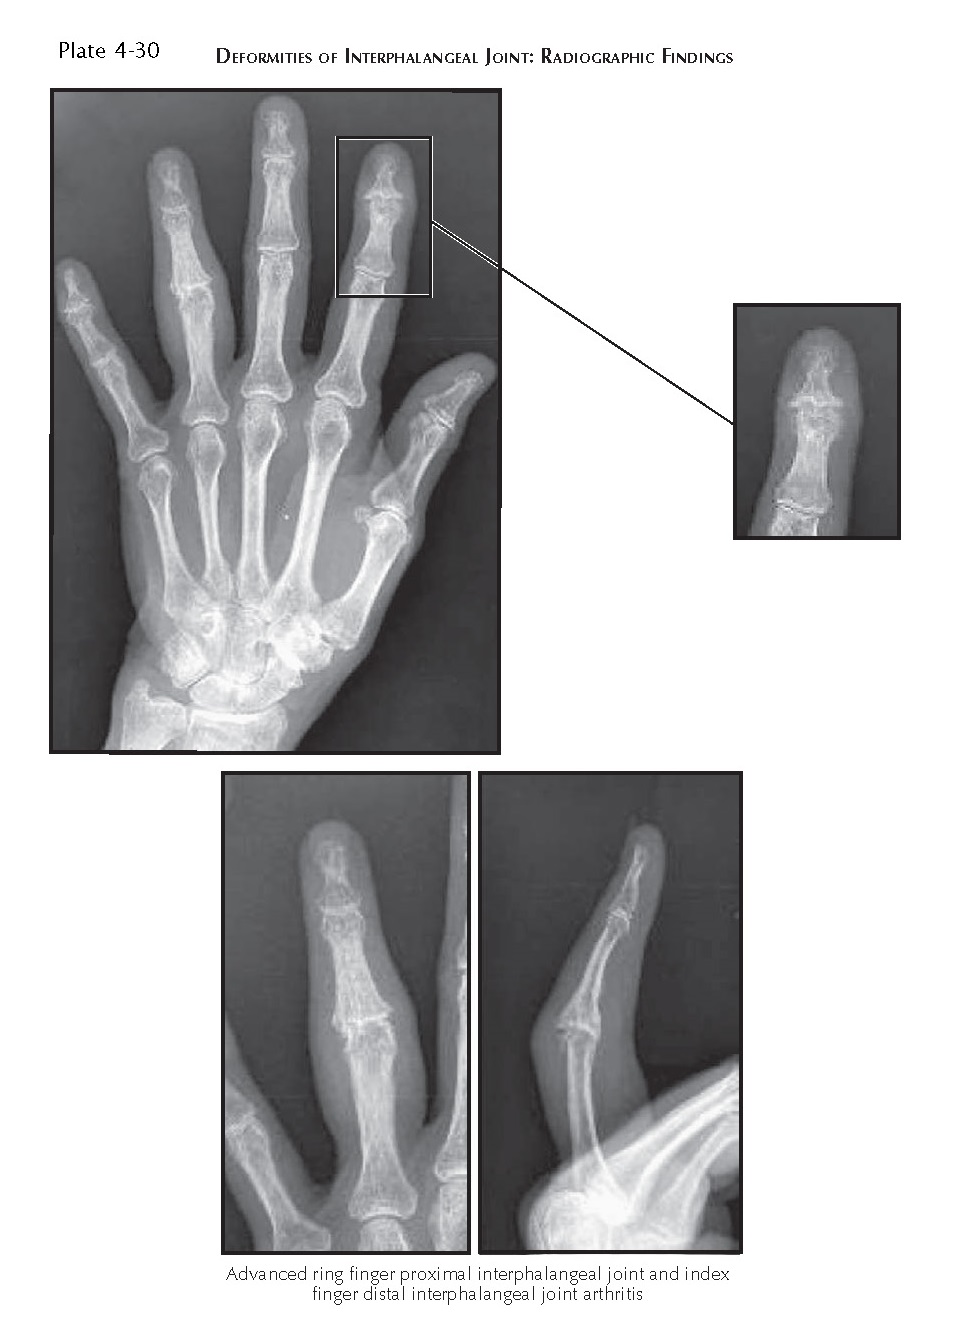

DEFORMITIES OF INTERPHALANGEAL JOINT pediagenosis Distal Interphalangeal Joint Boutonniere Diagnosis is made clinically with pip flexion and dip extension of a. A boutonniere deformity is a deformity of the fingers in which the proximal interphalangeal joint (pip) is flexed and the distal interphalangeal joint (dip) is. There also are multiple rheumatoid nodules over. It is often the result of an injury to the tendon that straightens the middle joint. Distal Interphalangeal Joint Boutonniere.